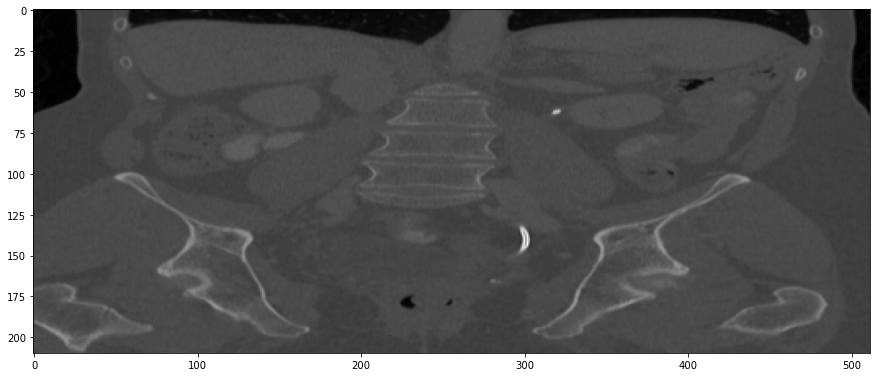

Refer to caption

(a) True Thick-slice image

(b) Simple Averaging

RMSE: 0.0250, PSNR: 38.0530

(c) Gaussian Averaging

RMSE: 0.1758, PSNR: 21.1182

(d) Direct Downsampling

RMSE: 0.0348, PSNR: 35.1697

(e) Proposed Simulation

RMSE: 0.0051, PSNR: 51.8504

Figure 3: Coronal-plane thick-slice image quality comparison across four simulation methods.